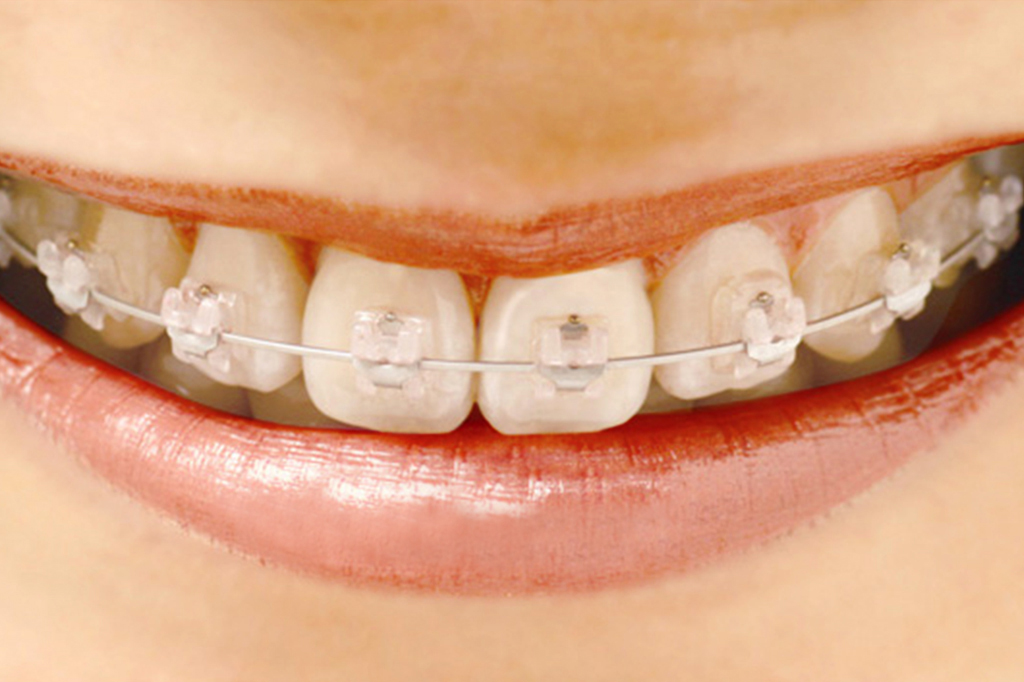

矯正治療の種類

部分矯正

気になる部位だけを矯正する治療法です。歯の隙間やねじれ、軽度の凹凸を整えることができます。来院間隔は治療内容や装置の種類によって異なりますが、歯を動かす場合は1カ月に1回程度です。

一般的な治療期間は約2~12か月、通院回数は約2~12回です。

全体の矯正治療に比べて治療期間や費用が抑えられますが、すべての症例に適用できるわけではありません。お口全体のかみ合わせを考慮して、全体の矯正をおすすめする場合もあります。